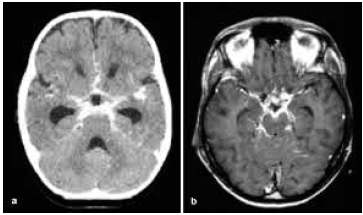

Paciente de 30 anos, previamente saudável, apresenta-se com um quadro clínico de duas semanas de evolução caracterizado por cefaleia persistente, febre baixa e rigidez nucal. O exame do líquido cefalorraquidiano (LCR) revela pleocitose linfocítica, hipoglicorraquia e hiperproteinorraquia.

A tomografia computadorizada (TC) do crânio encontra-se a seguir.

Das seguintes etiologias, a mais provável para os achados clínicos e laboratoriais nesse paciente é: